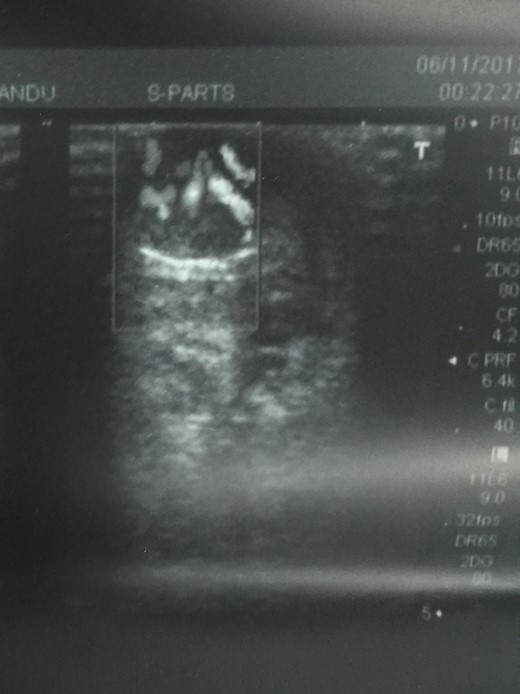

Ultrasound of the swelling revealed 2 × 1.5 cm well defined heteroechoic lesion with marked vascularity with both arterial and venous patterns of waveform in superior aspect of left nipple. Rest of the breast, areola and axilla were normal.